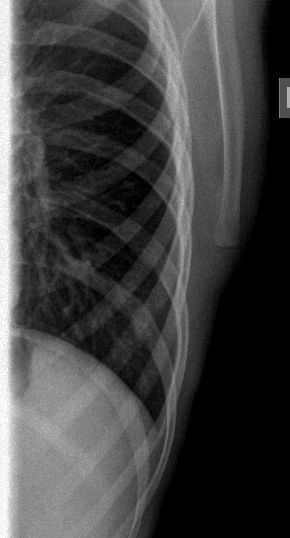

После УЗИ - сделал рентген, изменения в ребре есть, но в глаза не бросаются

Diagnosis of Ewing's Sarcoma is suspected

The irregularity of the rib shown sonographically suggests an osseous process like Ewing sarcoma. However, I have seen three patients with similar findings with destruction of the sternum and adjacent ribs mimicking a tumour of the bone but caused by an infiltration of a Hodgkin’s lymphoma. A lymphoma would also be more consistent with the lesions found in the spleen. Regarding the morphology and shape of the mass in the axilla, I think this is a lymphnode.

In any case, I would recommend excluding a lymphoma in addition to Ewing sarcoma. Infiltration of the sternum or ribs caused by Mb. Hodgkin is an important differential diagnosis, which is also suggested by the splenic lesions in that case that are possible but not typical for Ewing sarcoma.